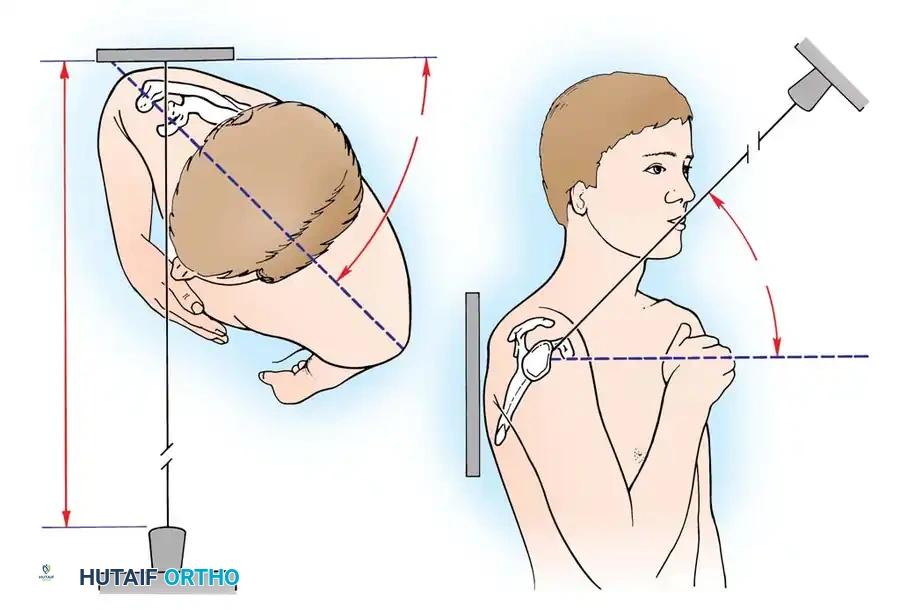

Patient Positioning and Anesthesia

The procedure is typically performed under general anesthesia supplemented with an interscalene regional nerve block for postoperative analgesia. The patient is placed in the beach-chair position with the head secured and the operative arm draped free to allow full manipulation. A mechanical arm holder is highly recommended to control rotation and abduction during the capsular shift.

- The arm is positioned in 30 to 45 degrees of abduction and 20 degrees of external rotation.